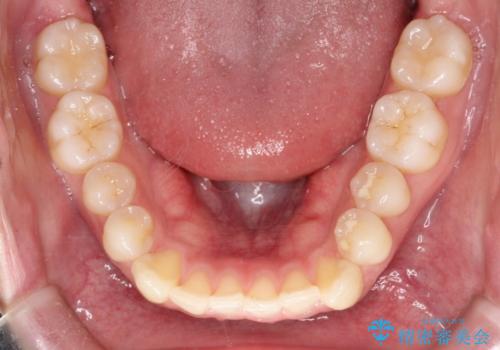

【クリア装置】前歯の凸凹を綺麗にしたい

- 前歯の凸凹を主訴に来院されました。

治療期間も短く大変満足していただきました。